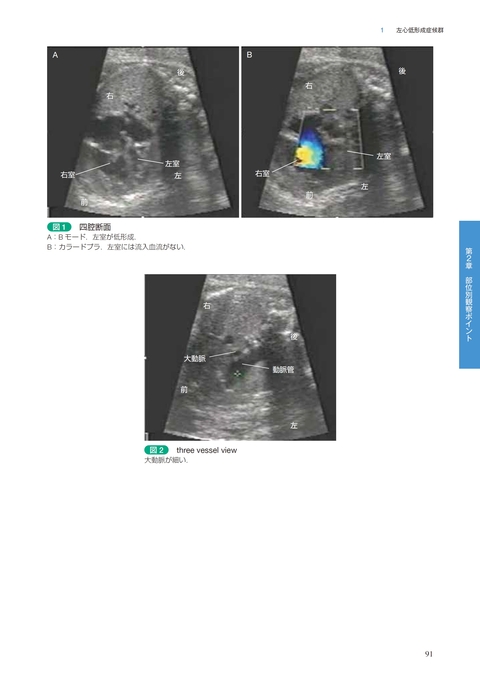

1)左心低形成症候群 / 和田誠司